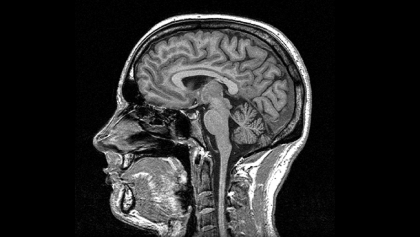

CT Scan and MRI Contrast Media

Multi-G has developed the first generic contrast media product range.

It allows us to provide imaging centers in Africa with affordable, high quality contrast media for CT scan and MRI.

Medical imaging is a high growth field because it allows much more advanced and reliable diagnostics.

Since the cost bears on the patient most of the time, it is crucial that affordable contrast media are made available so that patients have access to quality diagnostics, and imaging centers can develop their activity with reduced prices.